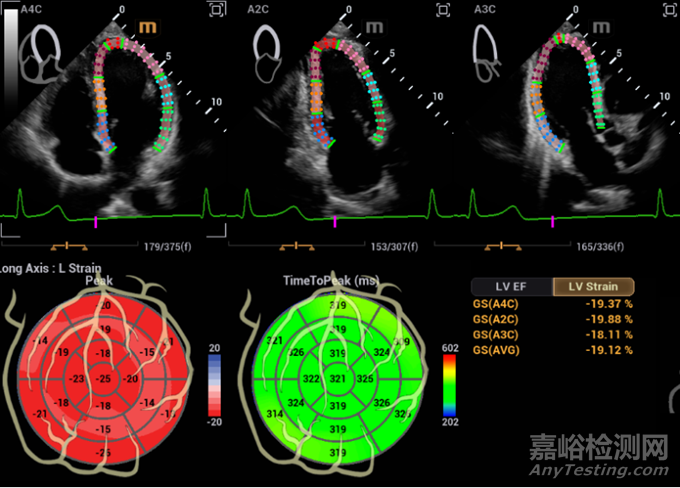

心血管超聲診斷系統(tǒng)鯤鵬 Recho R9具有更清晰的心血管影像,更精準(zhǔn)的心功能評(píng)估

和更高效的工作體驗(yàn)。

鯤鵬將具備Auto Strain自動(dòng)應(yīng)變?cè)u(píng)估技術(shù),智能化切面識(shí)別并追蹤室壁運(yùn)動(dòng),高效評(píng)估心肌運(yùn)動(dòng)狀況;還有Auto EF 自動(dòng)射血分?jǐn)?shù)測(cè)量,自動(dòng)識(shí)別心動(dòng)周期并描跡心內(nèi)膜邊界,計(jì)算左室心功能測(cè)量參數(shù),評(píng)估心臟收縮功能。

Auto Strain自動(dòng)應(yīng)變?cè)u(píng)估技術(shù)